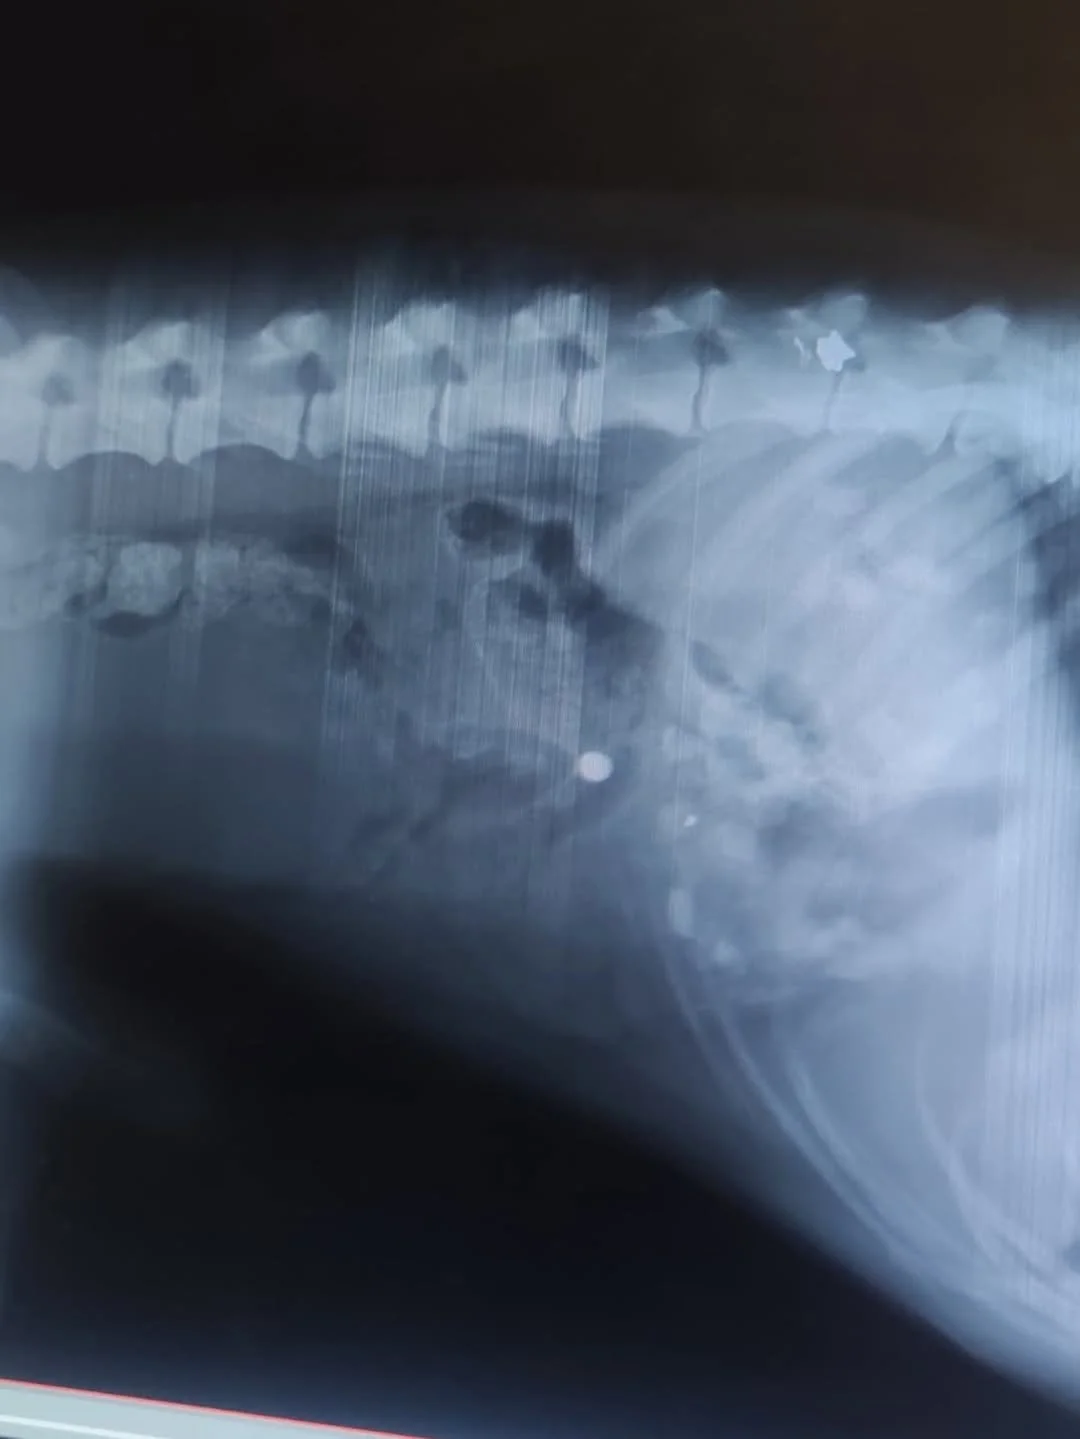

Once his trembling eased, the shelter team rushed him to the veterinarian. X-rays revealed the truth: multiple shotgun pellets lodged dangerously close to his spine. Each one was a cruel reminder of what he had endured, each one a risk to his fragile body.

And this was not the only case. The dog filled with shotgun pellets is one of many we have seen. Again and again, animals arrive at the shelter carrying the scars of deliberate shootings, their bodies riddled with metal fragments. The images and videos that follow are not isolated tragedies — they are part of a larger pattern of cruelty. Each survivor requires surgery, medication, and months of care, and each one deserves the chance to heal.